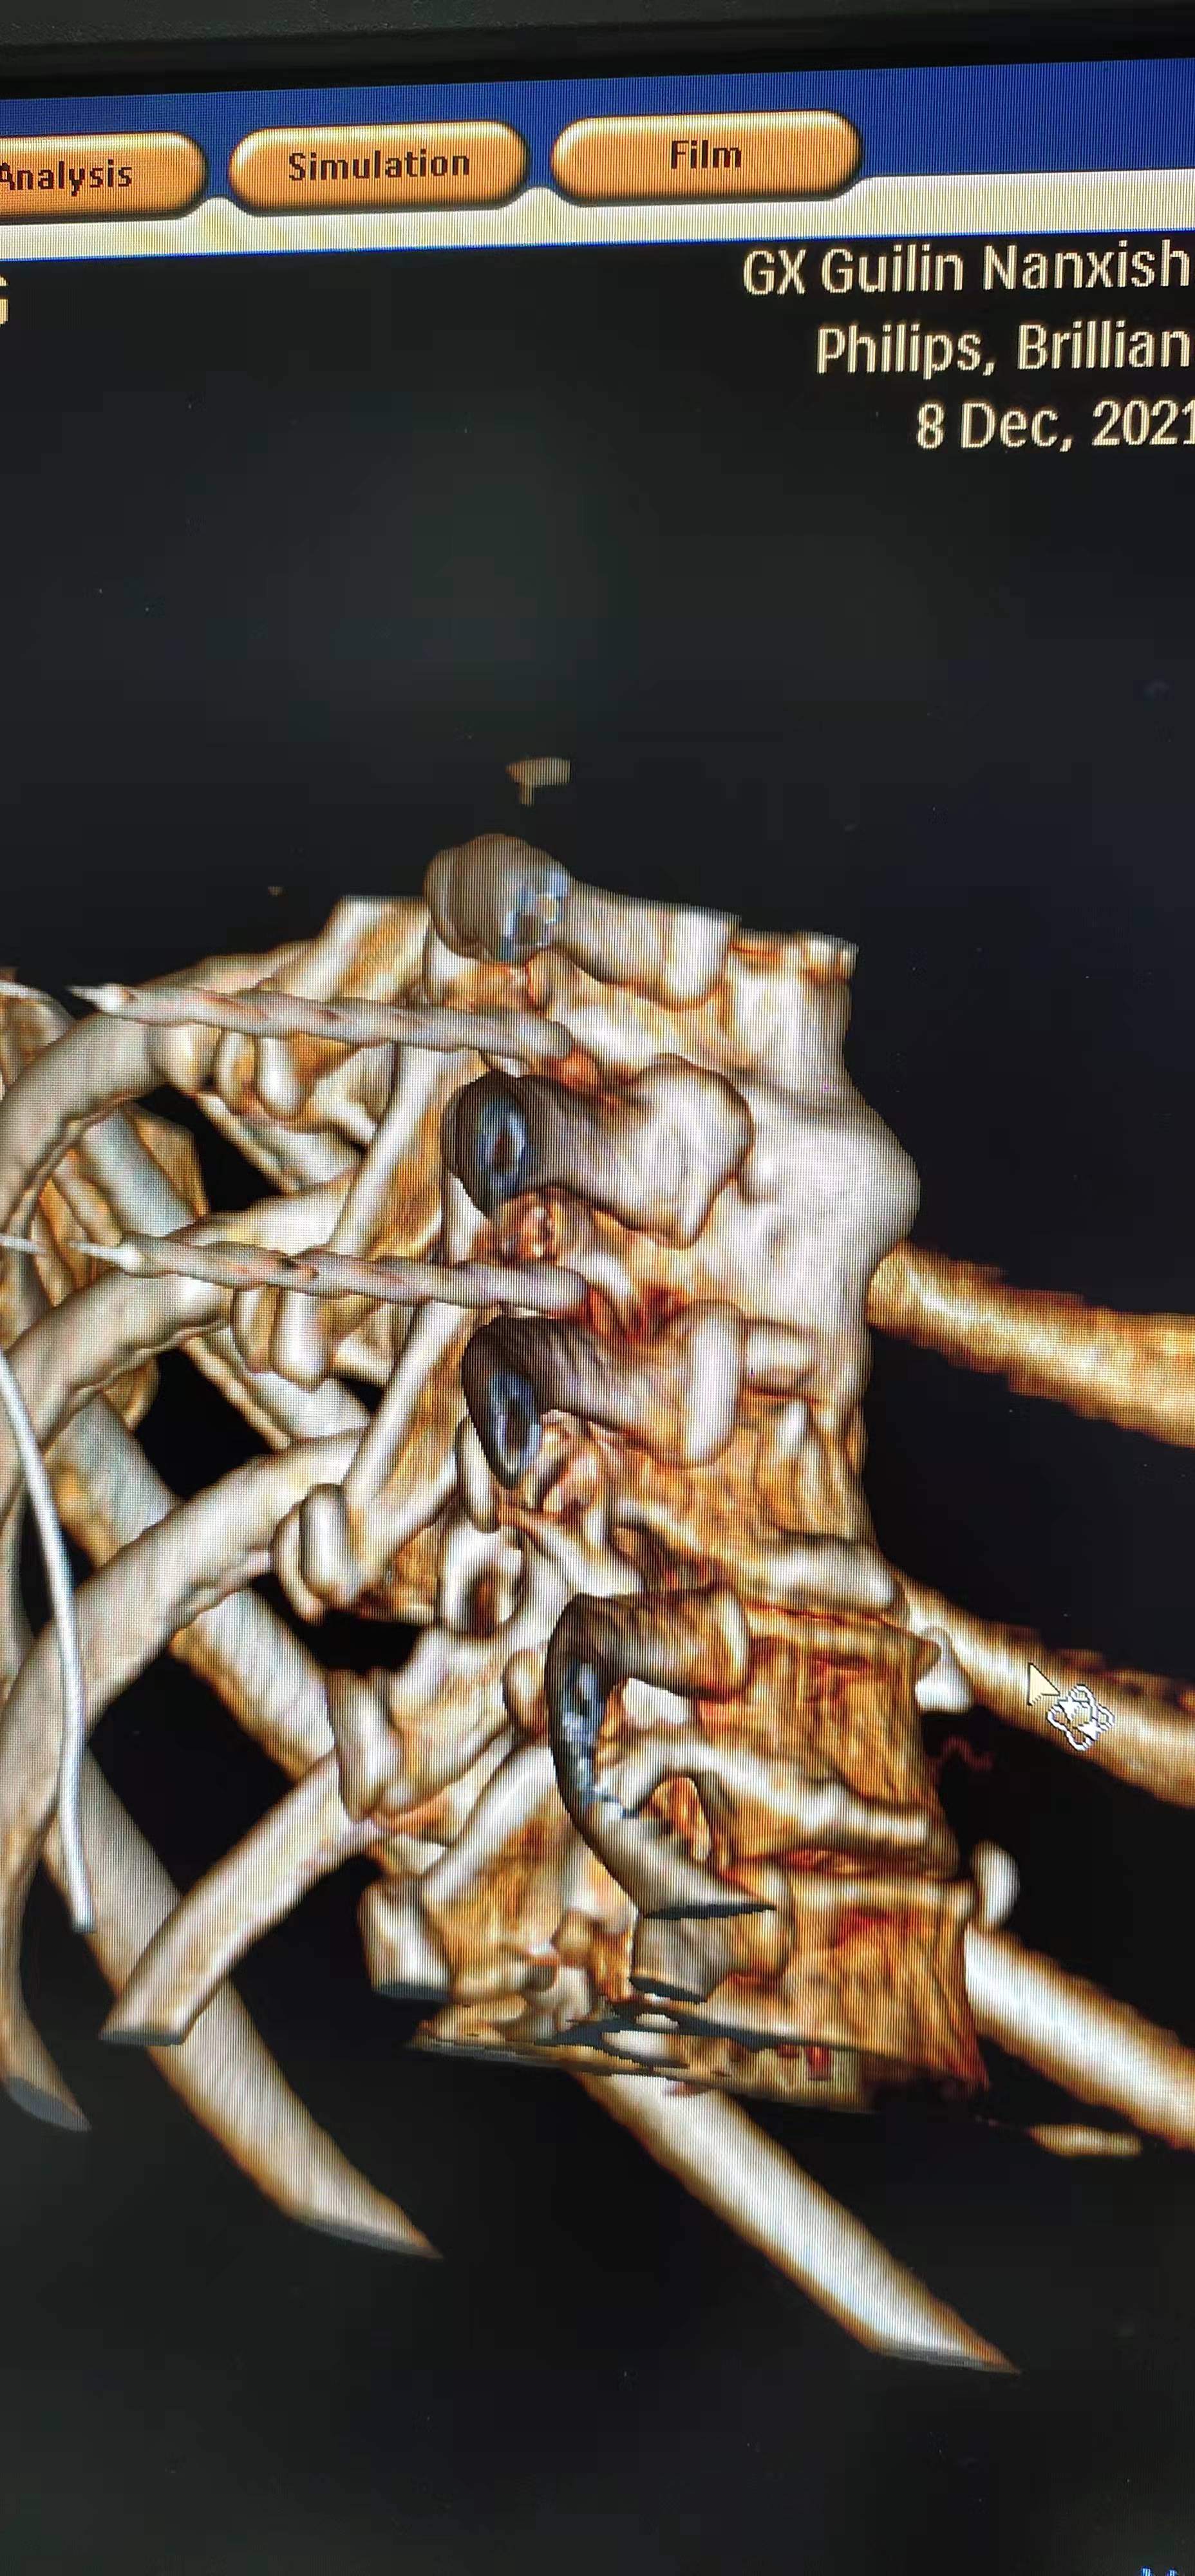

为达成这一目标,田文海主任团队依托该院 3D 打印中心,结合医院先进的大孔径 CT,利用 3D 打印技术可以个体化三维定位引导的优势,为该类患者研制了个体化导板(背根神经节定位穿刺导板),经过多次试验并改进,终于达到了极高的术中定位精准,术中 CT 的引导次数又原来的 5—7 次缩减到 2-3 次。手术时间也缩短到原来的 1/3。

尤其是多节段治疗的患者,更为明显。此外,因为 3D 导板技术使个性化精准穿刺,操作更为简单,学习曲线降低,降低了医生的学习难度,避免了因为远离背根神经节导致疗效不佳,让更多的患者达到最佳的疗效成为可能。